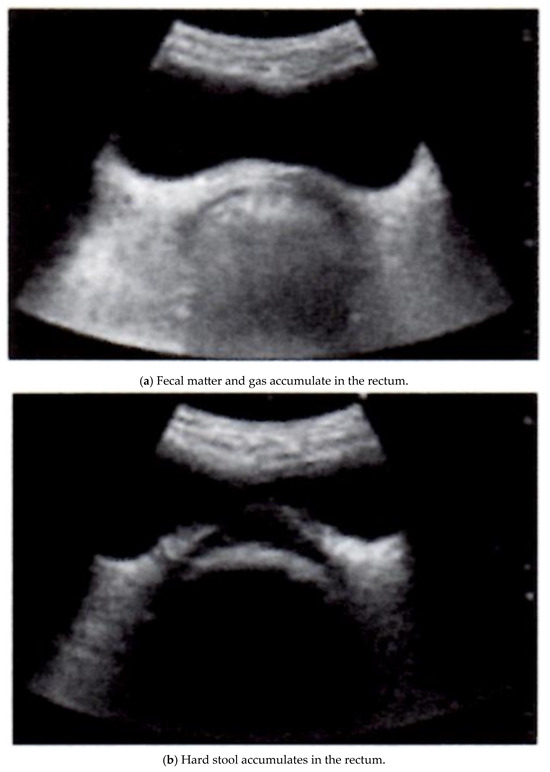

However, owing to recent improvements in device performance, the clinical application of noninvasive, low-cost, simple, and repeatable ultrasound imaging equipment for gastrointestinal diseases has attracted increased attention. Ultrasound-based methods have attracted particular attention because of their many inherent advantages, such as wide availability, bedside availability, and relatively low cost. Several ultrasound techniques have been developed using different excitation methods (Table 1) [24,32]. Several reports have described the clinical application of ultrasound imaging equipment for the treatment of chronic constipation [33,34,35,36]. In recent years, a research group consisting of multidisciplinary staff involved in chronic constipation treatment has proposed a simple functional evaluation method for chronic constipation treatment using rectal echocardiography [36]. This evaluation method classifies the state of fecal retention in the rectum into three patterns (Figure 1a–c). This image is quoted from Reference 36 with some modifications. The presence or absence of rectal fecal retention and the quality of the stool can be evaluated by recording a cross-sectional image of the rectum via ultrasound. In cases of fecal accumulation in the rectal lumen, echoes were reflected from the surface of the content located deeper than the bladder, and a half-moon-shaped hyperechoic area was visualized on a cross-sectional image (Figure 1a). In addition, when hard stool accumulates, acoustic shadows occur (most of the ultrasound waves are reflected by strong reflectors), and the ultrasound waves do not reach the distal side of the body. As a result, there is no sound behind the reflector. A crescent-shaped hyperechoic area is visualized, in which echo or hypoechoic activity is observed (Figure 1b) [37]. If the rectum was free of stool or gas, no obvious hyperechoic area was visualized. On cross-echo images, a circumferential hypoechoic area was observed as an empty intestinal tract (Figure 1c).

Figure 1.

Evaluation of fecal retention in the rectum using ultrasound imaging equipment (this image is from [36] with some modifications): (a) fecal matter and gas accumulate in the rectum. The presence or absence of rectal fecal retention and the quality of the stool can be evaluated by recording a cross-sectional image of the rectum via ultrasound. In cases of fecal accumulation in the rectal lumen, echoes are reflected from the surface of the content located deeper than the bladder, and a half-moon-shaped hyperechoic area is visualized on a cross-sectional image. (b) Hard stool accumulates in the rectum. When hard stool accumulates, acoustic shadows (most of the ultrasound waves are reflected by strong reflectors) do not reach the distal side of the body. As a result, there is no sound behind the reflector. A crescent-shaped hyperechoic area is visualized in which echo or hypoechoic activity is observed. (c) There is no retention of feces in the rectum. When the rectum was free of stool or gas, no obvious hyperechoic area was visualized. On cross-echo images, a circumferential hypoechoic area may be observed as an empty intestinal tract.